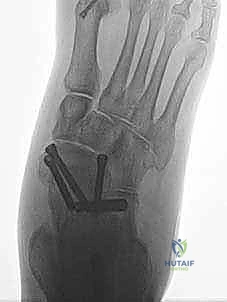

* الإصلاح المباشر (Direct Repair): إذا كانت أنسجة الرباط الممزقة ذات جودة جيدة (عادة في الإصابات الحديثة)، يقوم الدكتور هطيف بخياطتها مباشرة. يستخدم خطاطيف تثبيت عظمية (Suture Anchors) صغيرة جداً ومصنوعة من مواد متوافقة حيوياً (تذوب مع الوقت أو من التيتانيوم) لغرس الخيوط القوية في عظمة الكعب الإنسي، ثم يتم سحب الرباط الممزق وتثبيته بقوة في مكانه التشريحي الأصلي.

- إعادة البناء (Reconstruction): في الحالات المزمنة حيث يكون الرباط الأصلي قد تليف، تآكل، أو أصبح غير كافٍ للاستخدام، يلجأ الدكتور هطيف إلى تقنية "إعادة البناء". تتضمن هذه التقنية المتقدمة استخدام رقعة وترية (Graft)، إما من جسم المريض نفسه (Autograft - مثل أوتار الركبة أو وتر من القدم) أو رقعة صناعية متطورة. يتم حفر أنفاق ع